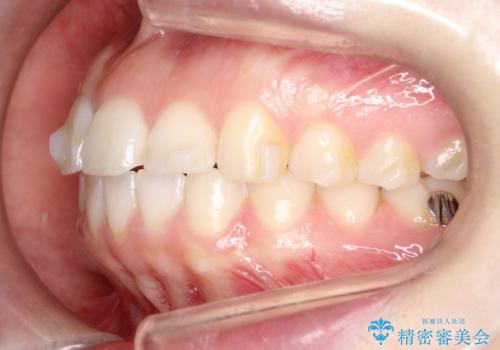

【インビザライン】前歯が出ているのを治したい

- 前歯が出ていることを主訴に来院されました。

前歯の突出感が改善され、満足していただきました。